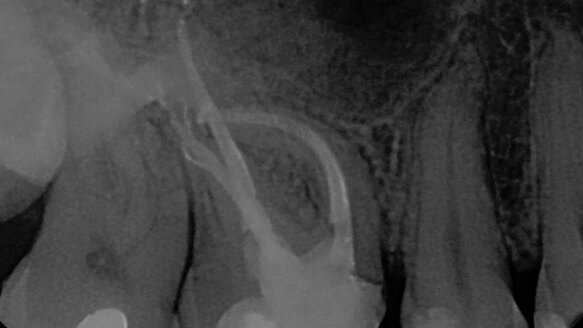

“GuttaCore is the first obturator with a cross-linked gutta-percha core,” said Scott Williams, senior brand manager for DENTSPLY Tulsa. “Since its initial launch in 2010, we’ve seen wide spread acceptance and adoption of GuttaCore among general dentists and a growing number of specialists. It’s exciting to see the doctor’s expression after filling with GuttaCore. They light up and smile when they see the complex apical anatomy open up and GuttaCore fill in areas where traditional cold gutta-percha stops.”

Two endodontic residency programs were selected as winners, based on the largest percentage of residents who submitted a case. A cash prize of $10,000 was awarded to the first- and second-place programs. In addition, representatives from both programs are joining DENTSPLY Tulsa, along with the most prominent endodontic opinion leaders, at the 2014 Endodontic Opinion Leaders Forum in Playa del Carmen, Mexico.

In addition to the residency program awards, residents were recognized for their individual submissions. Finalists were selected by a panel of judges, and winners were determined via voting on DENTSPLY Tulsa Dental Specialties’ Facebook page. The first place resident received $3,000 and is invited to present the winning case at the 2014 Endodontic Opinion Leaders Forum. The remaining top five residents all received cash prizes of $1,000. In addition, the top two alumni submissions also received $1,000.

- Grand Prize Winner - Dr. Brian Royle.